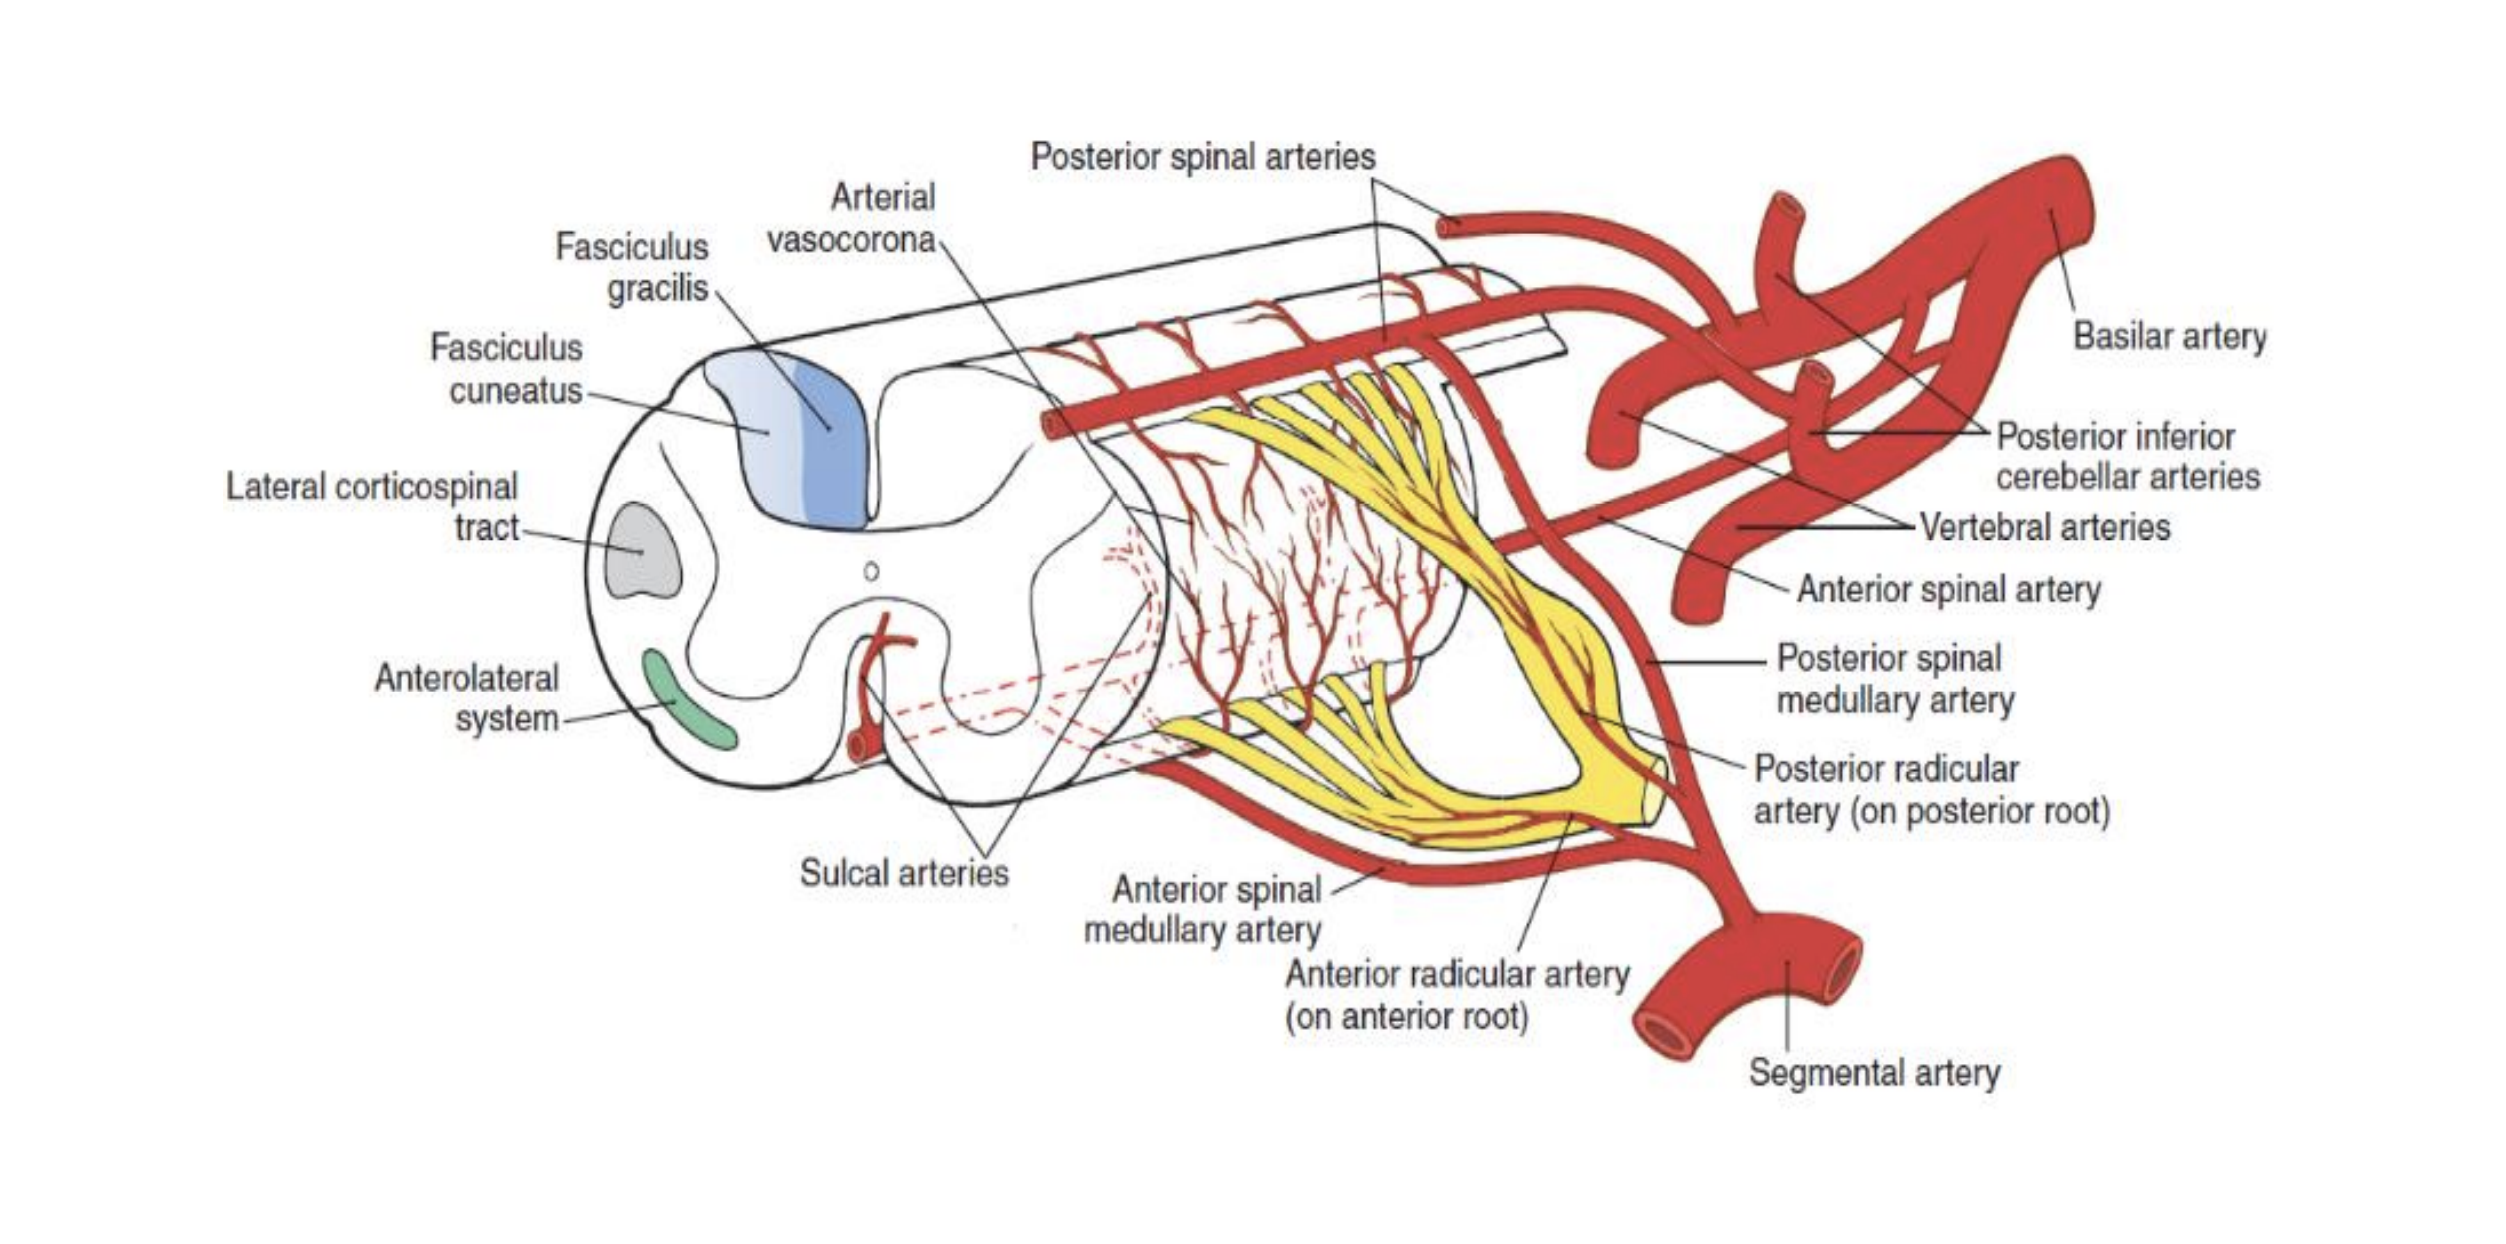

The arterial supply of the spinal cord + origins

Anterior spinal artery that originates inside the cranium from branches off the vertebral arteries.

Two posterior spinal arteries that originate in the cranium as branches off the vertebral arteries or the posterior inferior cerebellar arteries, and descend along the posterolateral sulci

The 8-10 segmental medullary arteries arise from the aorta.

The largest is the artery of Adamkiewicz in the lower thoracic region.

Segmental spinal arteries arise from vertebral and deep cervical arteries in the neck. The deep cervicals are branches from the subclavian artery that run up into the neck.

These branches go through the intervertebral foramina, and split into anterior and posterior radicular arteries.

The segmental arteries attach to the anterior and posterior spinal arteries.